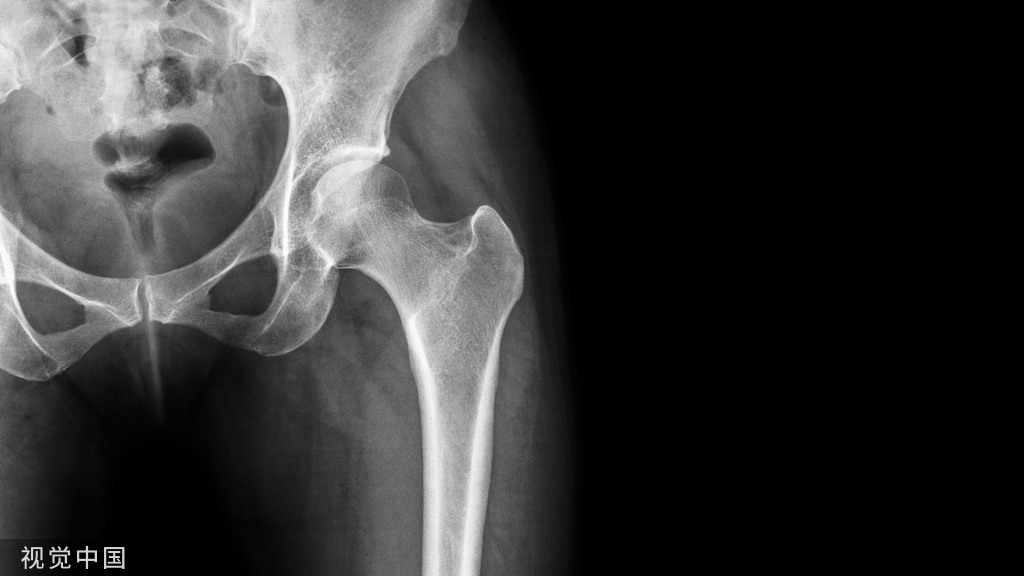

什么是髋骨骨折?怎么判断?

髋部处于人体最重要的关节部位,与多种骨骼、韧带、肌肉相连。通俗来讲,髋部就是大腿和臀部连接的部位,就是老百姓常说的胯部。髋关节又是连接人体躯干和下肢的重要枢纽,承载着人体上部的重量,也是人体最大、最重的关节。

髋骨骨折主要是指髋臼骨折和股骨近端骨折,其中股骨颈骨折和股骨转子间的骨折属于最为常见的类型,约占老年人髋骨骨折的90%以上。对于老年人而言,髋骨骨折其实就意味着死亡,因为在保守治疗下,1年的生存率仅为50%。股骨颈骨折大部分是由突然跌倒或是外来暴力等原因引起的,骨折发生后,患者会出现髋部疼痛、不敢站立、患肢缩短等表现,但是也有一些在伤后仍能走路或骑自行车的情况,所以要仔细检查。